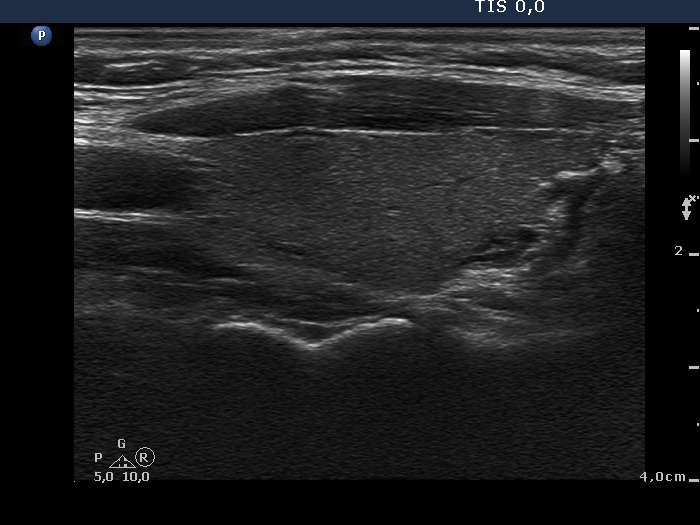

Second examination 9 months later (2nd row of images)

Clinical data: The patient had no complaints except for a 6 kg weight in gain.

Palpation: unchanged.

Results of blood tests: euthyroidism on daily 10 mg methimazole (TSH 3.58 mIU/L, FT4 12.7 pM/L).

Ultrasonography: Compared with the first examination, the thyroid has decreased in size and the echo structure became less hypoechogenic. The vascularization remained unchanged.

Suggestion: daily 5 mg methimazole.